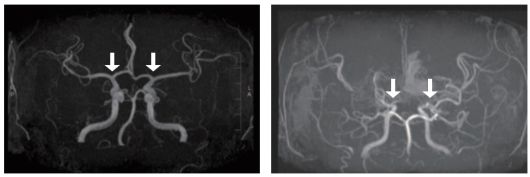

[사진 왼쪽부터] 정상 및 모야모야병 환자의 뇌혈관 |

모야모야병은 뇌로 혈액을 공급하는 혈관이 원인 없이 점차 좁아지는 만성 진행성 뇌혈관질환이다. 10세 전후 소아와 40세 전후 성인에서 주로 발병하며, 부작용으로는 뇌혈관이 막히거나 파열되는 허혈성·출혈성 뇌졸중이 있다. 그중 소아 환자는 성인보다 허혈성 뇌졸중이 빈번하고, 장기 예후가 대체로 양호하지만, 3세 미만 어린 연령에서는 진행이 빨라 주의가 필요하다. 그러나 국내 소아 모야모야병 인구를 분석한 장기간 역학 자료는 제한적이었고, 이들의 예후를 분석한 결과도 드물었다.